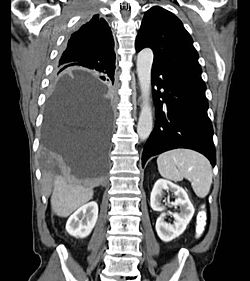

Symptoms - chest pain and shortness of breath (often associated with hemorrhagic effusion in the pleural cavity).

Examination methods - X-ray, CT, HRCT, biopsy of the pleura (peritoneum), examination of exudate .